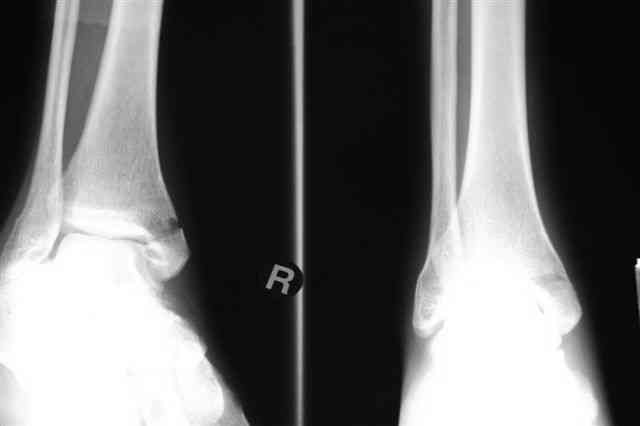

Лодыжку так ипрооперировал двумя 3.5 мм шурупами пришлось открыть - закрыто не удалось адекватно отрепонировать, при открытии - надкостничная

интерпозиция.

Бедро фиксировал длинной DCS.

В приложении отправляю послеопер. снимки бедра и лодыжки обсуждаемого вчера больного.